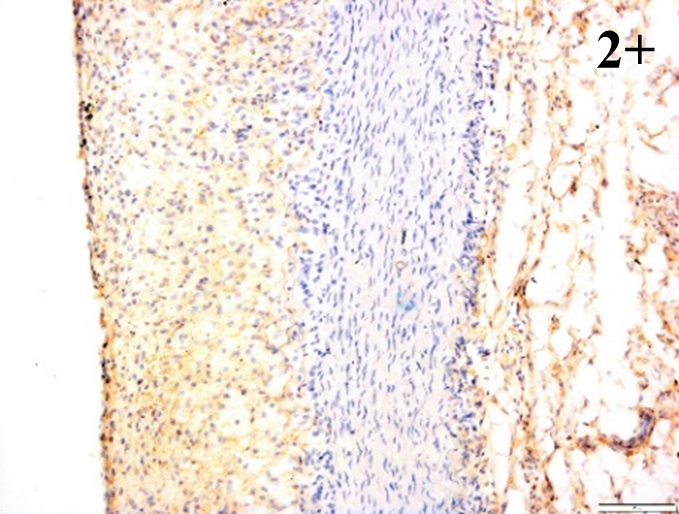

According to the percentage endothelial staining of cells, semi-quantitative

scores were applied. Score: 0 (negative); 1+ (1–10% positive cells); 2+

(11–25% positive cells) and 3+ (